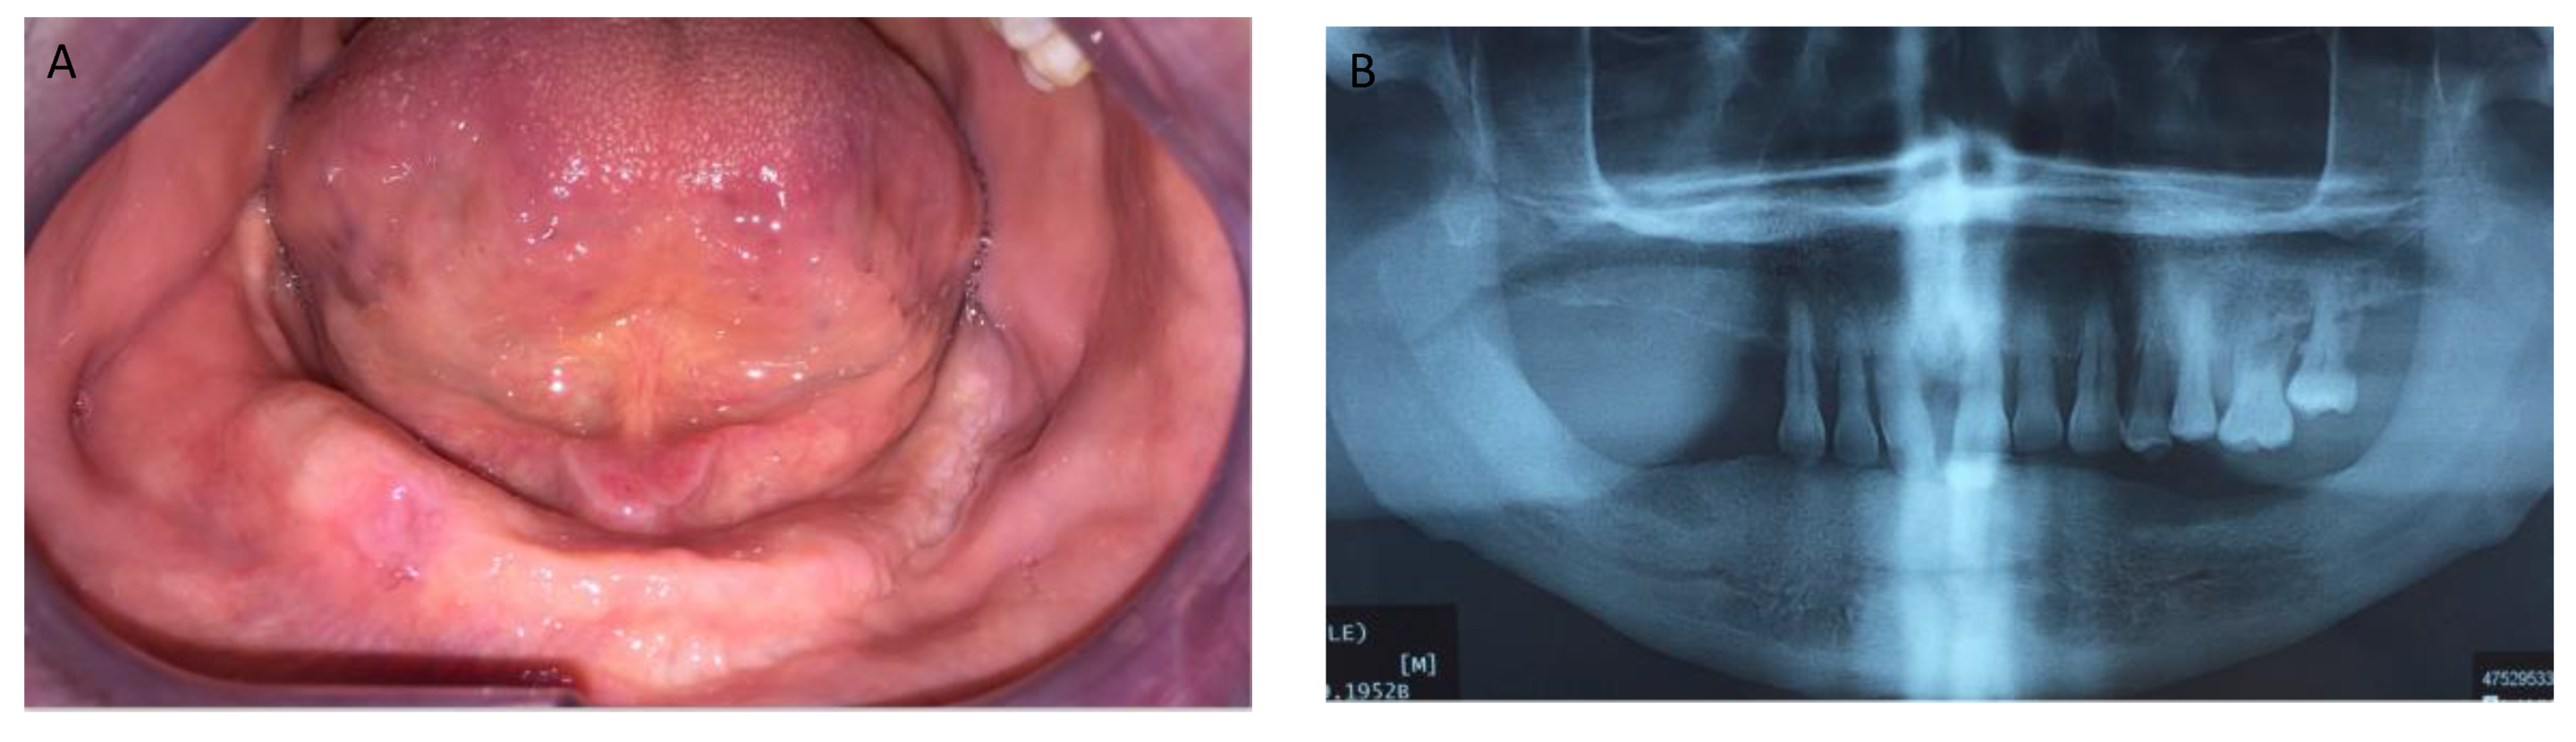

Figure 1, Figure 2, Figure 3, Figure 4, Figure 5, Figure 6 and Figure 7 show the progress of treatment in one of the patients of the test group. In Figure 3 reduction of the medullar space is visible, that may create a chronic ischemic area susceptible to necrosis.

Figure 1.

Pre-operative intra-oral view from a MRONJ patient with bilateral defect. (A) left side; (B) right side.

Figure 2.

Pre-operative orthopantomography of the same MRONJ patient showing bilateral defect; (A) shows the panoramic view; (B) shows more detail of the right side of the mandible.